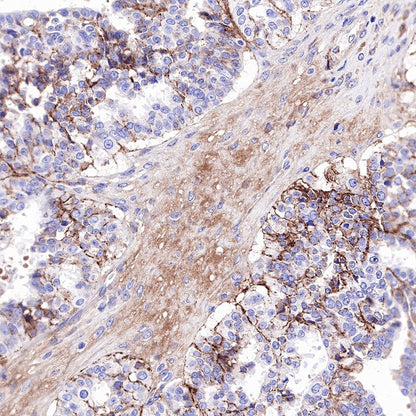

IHC shows positive staining in paraffin-embedded human ovarian cancer. Anti-CD81 antibody was used at 1/200 dilution, followed by a HRP Polymer for Mouse & Rabbit IgG (ready to use). Counterstained with hematoxylin. Heat mediated antigen retrieval with Tris/EDTA buffer pH9.0 was performed before commencing with IHC staining protocol.